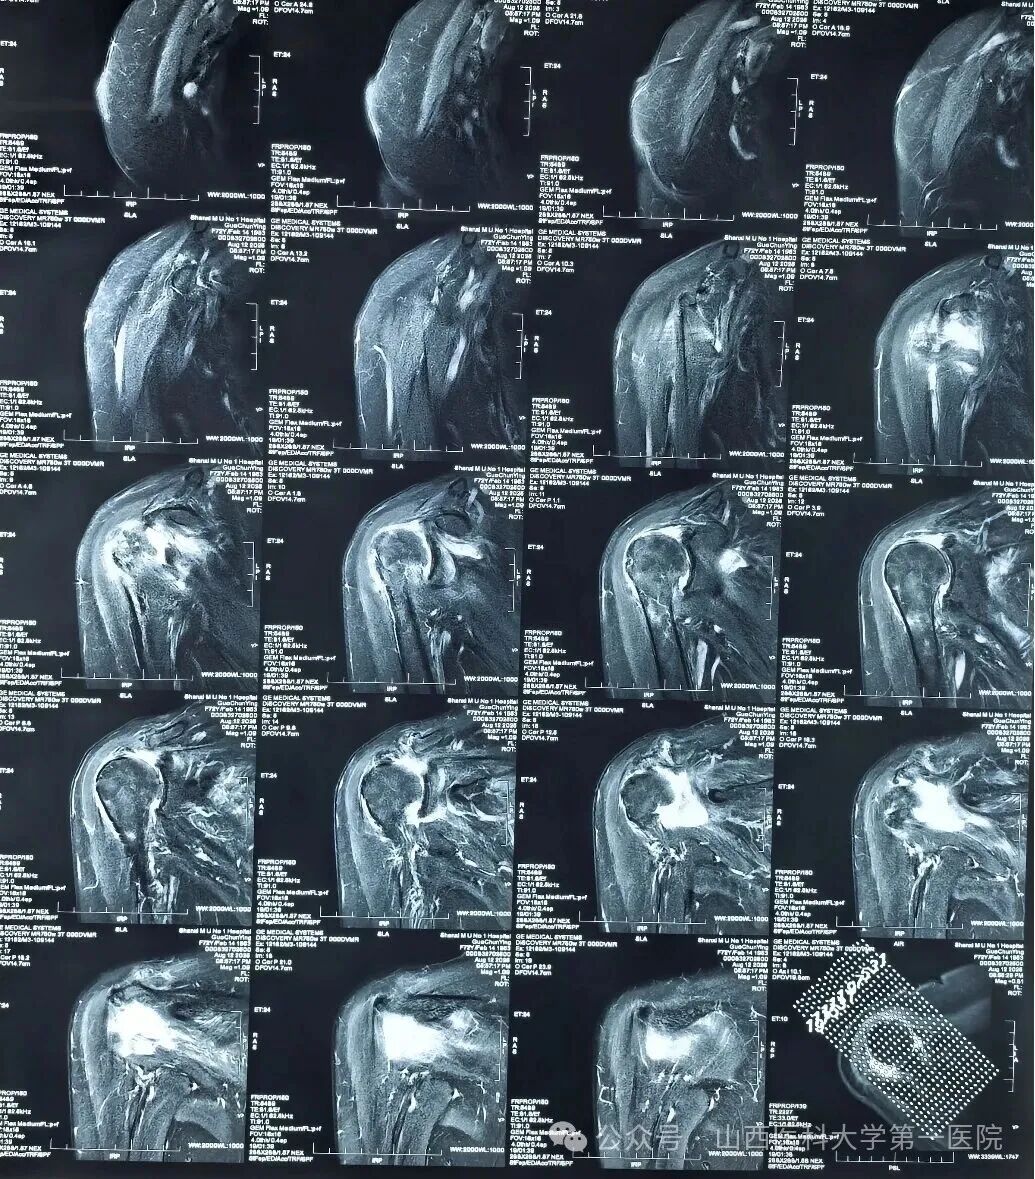

术前右肩MRI显示巨大间隙撕裂